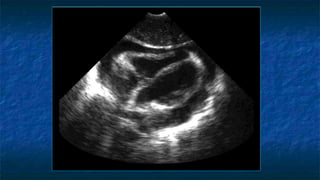

1) Subxiphoid exam

 Probe placed

 Transversally

 Midline plane

 Just below subxiphoid region

 Probe facing towards patient’s right

FAST: Subxiphoid exam

 Normal Anatomy

 Liver at very top of screen

 Epicardial fat vs. effusion

 Thin layer anterior to

RV

 Not present posterior

to LV

Normal Subxiphoid exam